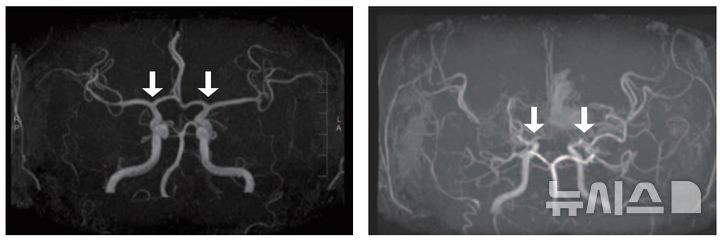

출근길 전국 곳곳에 미세먼지가 나쁨 농도를 보이고 있다. 미세먼지는 소아 천식, 비염 등 각종 호흡기 질환 등을 유발할 수 있어 주의해야 한다. 16일 기후에너지환경부에 따르면 전날 오후 5시부터 충청권·전북 지역에 초미세먼지 위기경보 '관심' 단계가 발령됐다. 미세먼지 농도는 수도권, 강원 영동, 충청권, 광주, 전북, 대구는 '나쁨'으로 예상된다. 미세먼지는 소아의 여러 호흡기 질환을 유발할 뿐만 아니라, 천식과 알레르기 비염 등 알레르기 질환들의 증상이 심해질 수 있으며, 장기적으로는 폐 기능 저하로 이어질 수 있으므로 민감군으로 각별한 주의가 필요하다. 초미세먼지는 상대적으로 크기가 작아 폐 깊숙이 침투하여 소기도와 폐포에 침착할 수 있으며, 혈관을 통해 다른 장기에도 영향을 줄 수 있다. 역학연구에서 대기 중 PM10, PM2.5, PM0.1, 질소산화물(NO₂) 농도가 증가할수록 피부 장벽을 손상시키고 산화스트레스를 높여 염증반응을 증폭시키기 때문에, 기저 아토피 피부염을 가진 환아에서 가려움, 홍반, 수면장애 등의 증상이 유의하게 악화된다는 결과가 반복해서 보고된 바 있다. 기관지폐이형성증, 선천성 폐기형, 선천성 심질환과 동반된 폐고혈압 등 선천성 폐질환이 있는 소아는 정상적인 폐기능을 보이는 폐 용적이 상대적으로 적으므로 같은 미세먼지 노출에도 산소포화도 저하, 호흡곤란, 감염 악화가 더 쉽게 나타난다. 최근 국내 코호트 분석에서도 소아기 미세먼지와 기체상 오염물질 노출이 폐 성장 지연과 호흡기 감염 증가와 연관된다는 보고도 있다. 그러므로 미세먼지 농도가 높은 날에는 되도록 외출을 피하고, 불가피하게 외출해야 한다면 아이 연령대에 맞는 보건용 마스크를 착용해야 한다. 실내에서는 공기청정기를 사용해 실내 공기 질을 관리하며, 주기적으로 창문을 열어 실내를 환기하되, 단, 미세먼지 농도가 나쁠 때는 환기 시간을 최소화한다. 물을 충분히 마시고, 비타민 C 등 항산화물질이 풍부한 과일과 채소를 섭취한다. 미세먼지가 기관지 점막을 건조하게 해 감염성 질환에 취약해질 수 있으므로, 인플루엔자가 유행인 계절에는 예방접종을 하는 것이 권고된다. 이민정 가톨릭대학교 서울성모병원 소아청소년과 교수는 "천식과 같은 기저질환이 있는 아이라면, 정기적인 흡입제·조절제 복용, 증상일지 작성과 정기적인 폐기능 추적을 통해 오염도 변화에 따른 증상 패턴을 함께 관리하는 것이 필요하다"고 말했다.